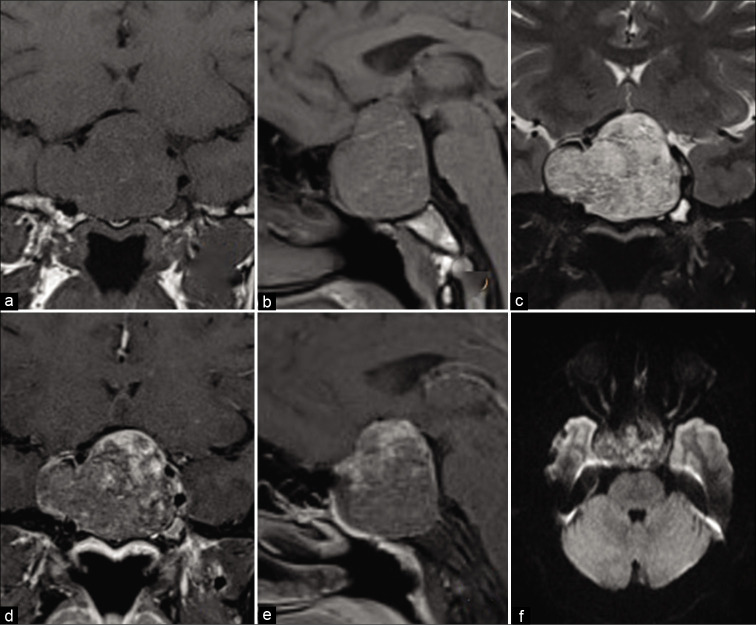

静脉注射造影剂的鞍区磁共振成像显示鞍区/鞍上/鞍旁较大肿块,T1图像呈不均匀低信号,T2图像呈中等高信号,DWI图像呈中央小面积扩散限制,增强后呈轻度斑片状强化。它的前后、头尾部和横向尺寸分别约为36x41x50 mm。病变完全包裹右侧颈内动脉海绵窦段和床突段,部分包裹右侧床突上段和左侧海绵窦段。病变还对邻近的结构产生肿块效应,表现为肿瘤隆起和三脑室底,视神经和视交叉的颅内段被拉伸并与病变分离。垂体和垂体柄看不见【图2】。

图2:术前核磁共振图像。(a)冠状面T1,(b)矢状面T1,(c)冠状面T2,(d)冠状面后对比,(e)矢状面后对比,(f)病变的轴位DWI图像显示不均匀的低T1信号、中高T2信号、斑片状后对比增强,中央区域扩散受限。